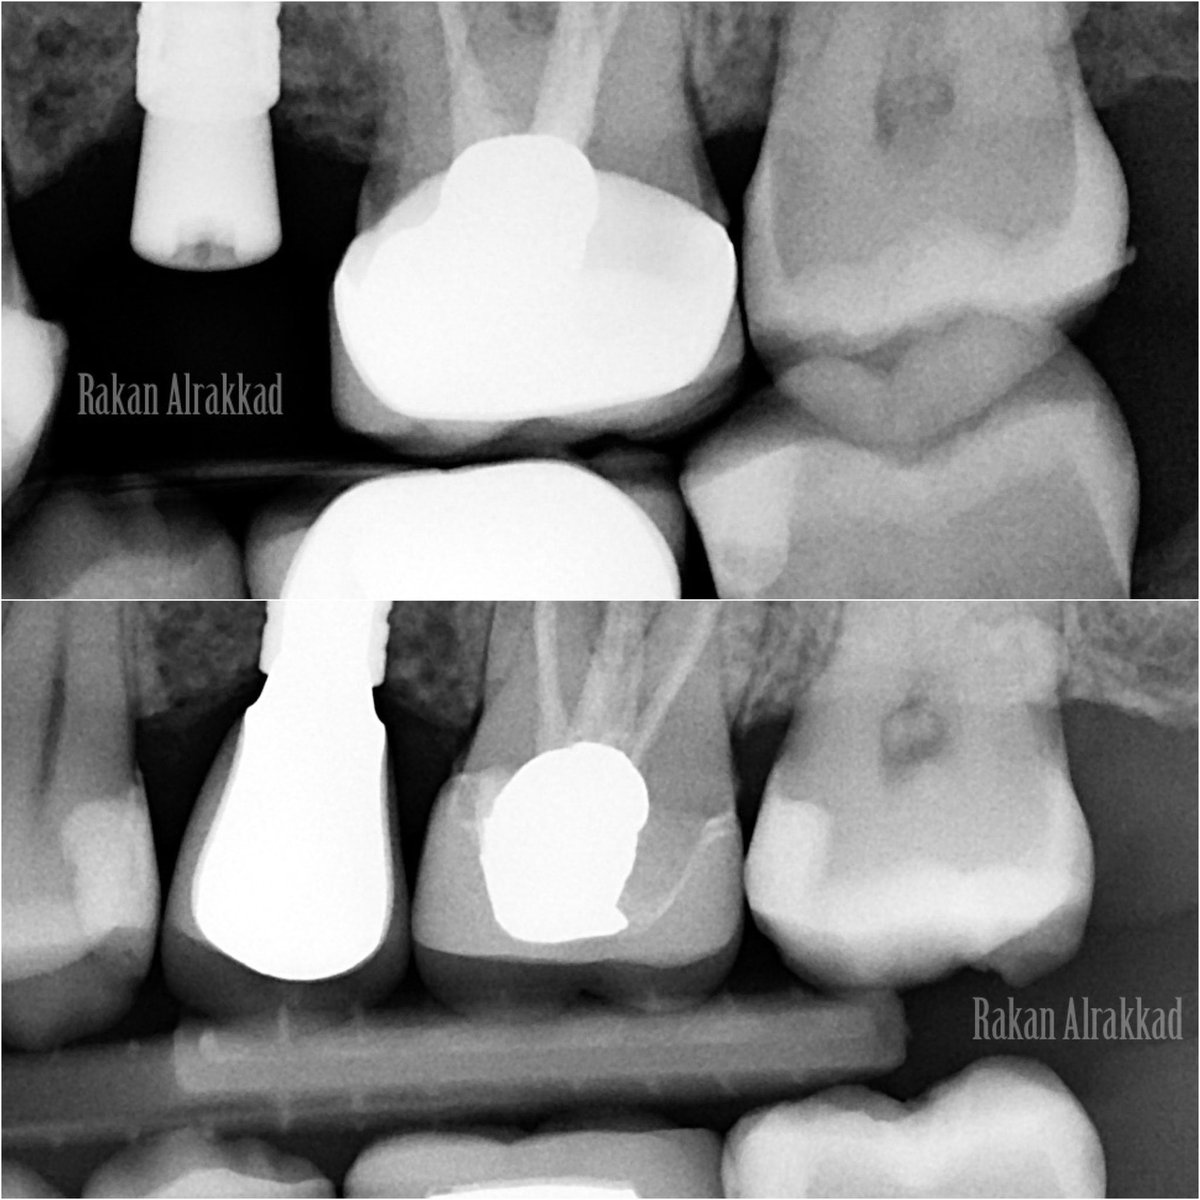

علاج عصب مع الحفاظ على التلبيسة 👌🏻 RCT through the crown done with conservative access #46 was SIP with intact crown 👑

علاج عصب مع الحفاظ على التلبيسة 👌🏻

RCT through the crown done with conservative access

#46 was SIP with intact crown 👑